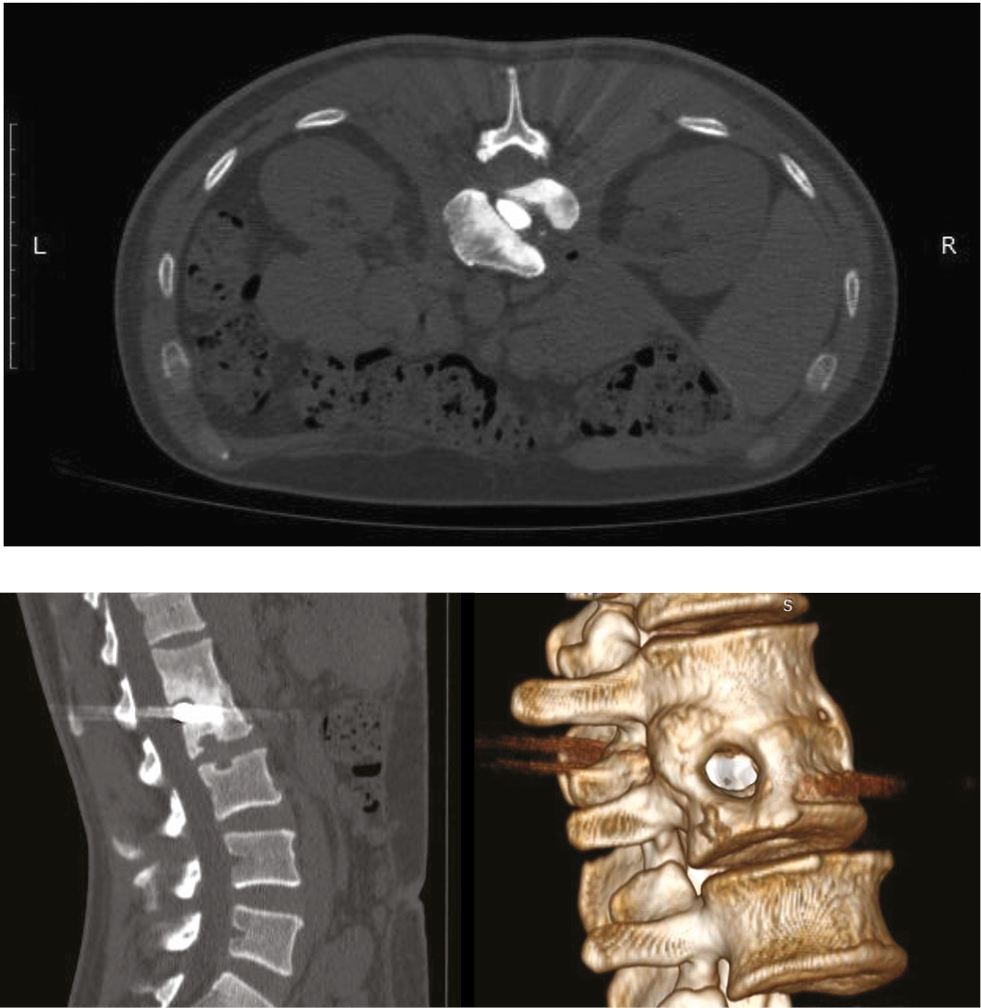

При выполнении компьютерной томографической фистулографии, во время последнего рецидива забрюшинной флегмоны, было выявлено наличие свищевого хода между полостью флегмоны и областью расположения инородного тела. С учетом возможной причинно-следственной связи с рецидивирующей флегмоной пациенту было рекомендовано удаление инородного тела из позвоночника. После проведенного дообследования (выполнения дооперационных компьютерных томограмм, рис. 2) пациент госпитализирован в клинику нейрохирургии ВМА для планового оперативного вмешательства.

Рис. 2. Дооперационные компьютерные томограммы поясничного отдела позвоночника пациента П. На сагиттальных срезах и 3D-реконструкции визуализируется сформировавшийся костный блок между телами LI и LII

Fig. 2. Preoperative computed tomograms of the lumbar spine of patient P. On sagittal sections and 3D reconstruction, the formed bone block between bodies LI and LII is visualized

Внешний вид послеоперационной раны и контрольные компьютерные томограммы представлены на рис. 6.

Рис. 6. Внешний вид послеоперационной раны: a — 7-е сутки после вмешательства; b — послеоперационные компьютерные томограммы в аксиальной проекции

Fig. 6. Appearance of the postoperative wound: a — 7th day after the intervention; b — postoperative computed tomograms in axial projection